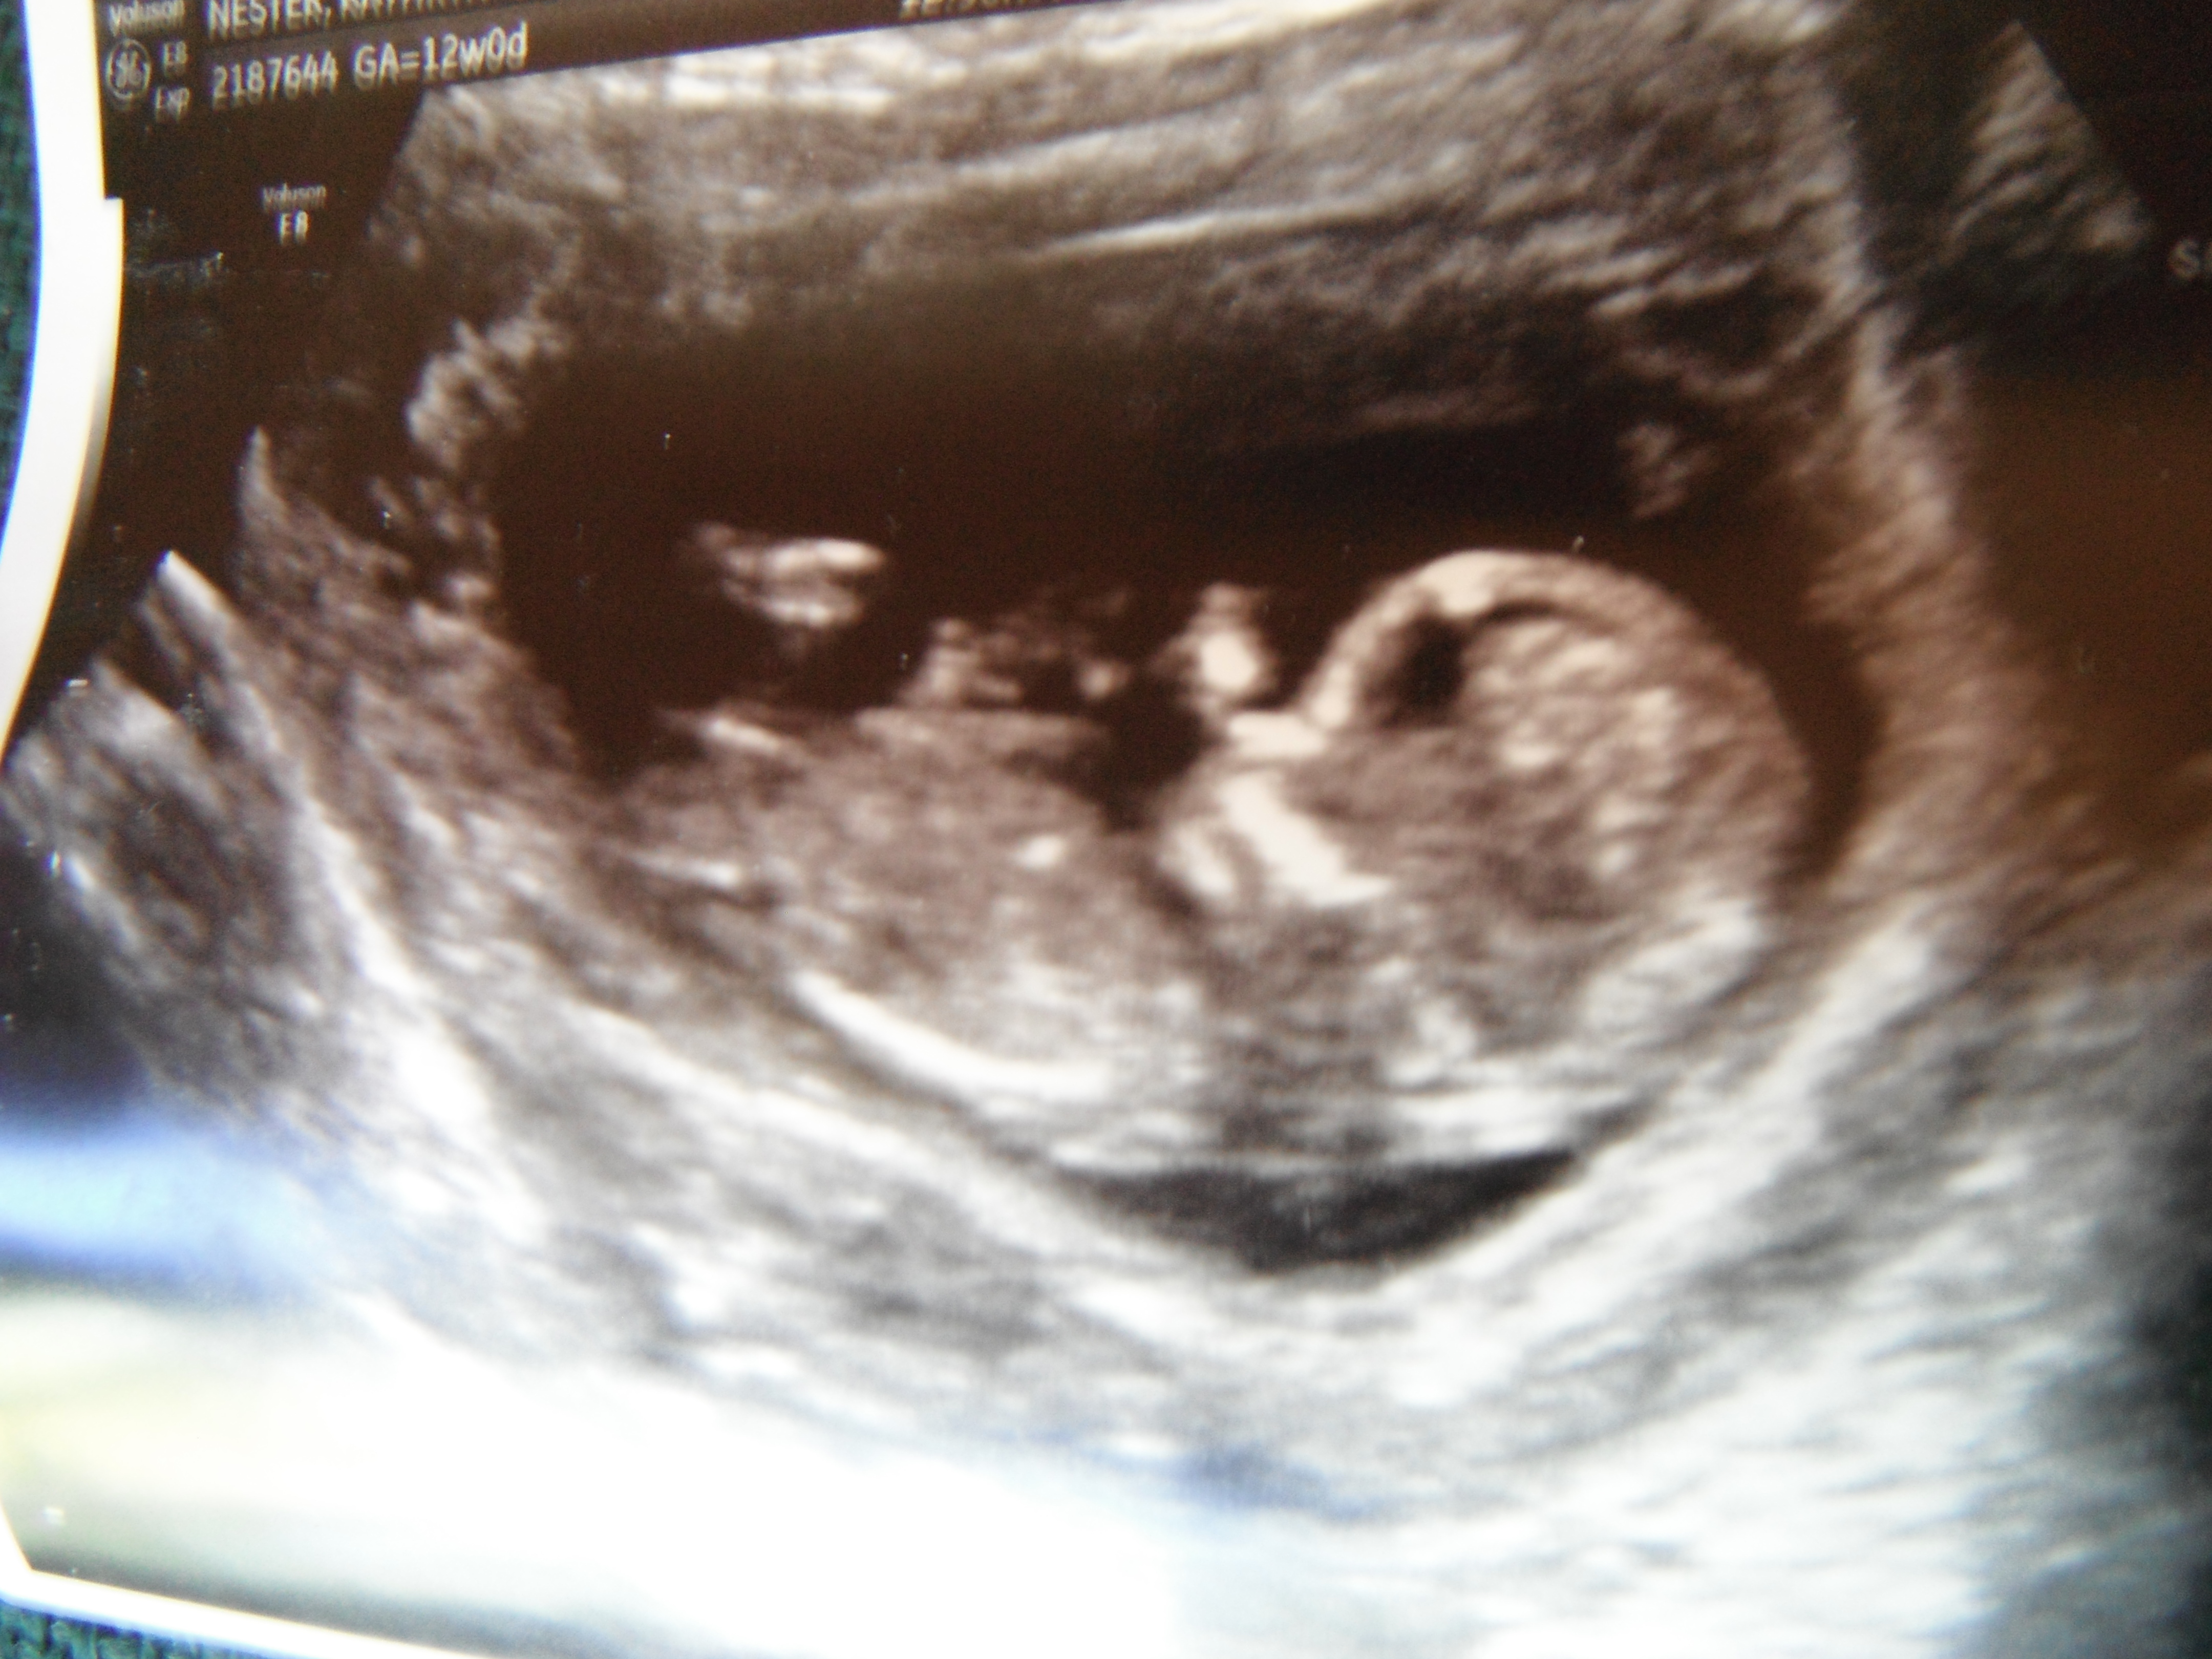

would love a NUB GUESS on our "whoops we got pregnant before we could sway" baby! :)

Atomic, I said I'd be back with gender... though at 12 weeks it's just a guess... ;)

Tech didn't want to say anything - but after I coerced her...she said, "Initially I thought I saw boy parts, then as the scan went on, I mentally changed my guess."

Hard to tell so early...but is anyone else brave enough to give me their thoughts?